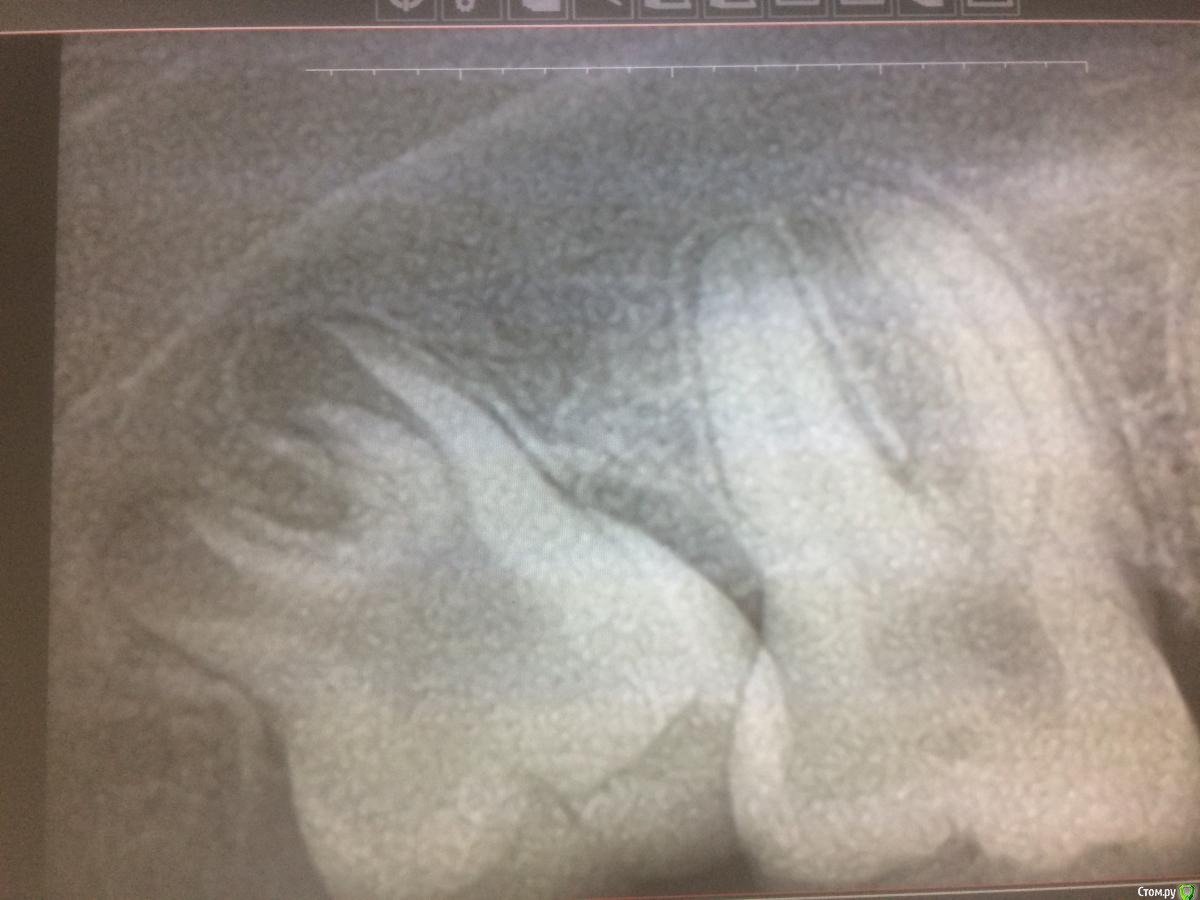

xMeDx Опубликовано 18 июня, 2019 Поделиться Опубликовано 18 июня, 2019 Здравствуйте коллеги.Вопрос по 8-ке.Ждать пока сформируется или лучше сейчас удалить ?Есть подвижность 7-ки. Ссылка на комментарий

red_butler Опубликовано 18 июня, 2019 Поделиться Опубликовано 18 июня, 2019 удалять сейчас 7 Ссылка на комментарий

TiAn Опубликовано 18 июня, 2019 Поделиться Опубликовано 18 июня, 2019 Удаляйте, пока корни не сформировались Ссылка на комментарий

Irouil Опубликовано 18 июня, 2019 Поделиться Опубликовано 18 июня, 2019 Удаляйте, кортикалки над ней уже нет Ссылка на комментарий

vgraev Опубликовано 20 июня, 2019 Поделиться Опубликовано 20 июня, 2019 легче будет сейчас убрать, поскольку верхушки не сформированы. зачем откладывать на завтра то,что можно сделать сегодня)) Ссылка на комментарий